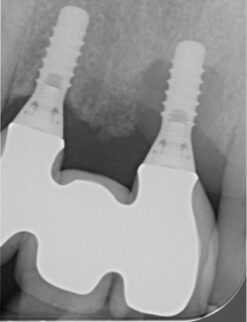

Hieronder laten we een perfecte casus zien van een verontreinigd implantaatoppervlak dat is glad gemaakt met behulp van NiTi brushes en Perisolv. Daarna is er opgebouwd met hyaluronzuur, smartgraft en een membraan. Tot slot heeft de behandelaar het geheel twee maanden laten genezen met een healing abutment. De resultaten op de foto's hieronder spreken voor zich.